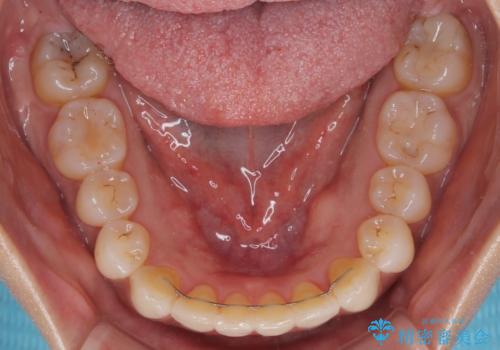

前歯のクロスバイト インビザラインによる矯正治療

- 上下のクロスバイトと前歯のデコボコを気にして来院された患者様です。

インビザラインを用い、IPR(歯と歯の間を削る)と歯列全体を拡大させることで、歯並びを整えていくこととしました。

インビザライン特有の、治療後半に奥歯が咬み合わないという事象が長引きました。

咬み合わないときの対処方法は色々とありますが、ゴムかけなどを活用して噛めるようにしました。